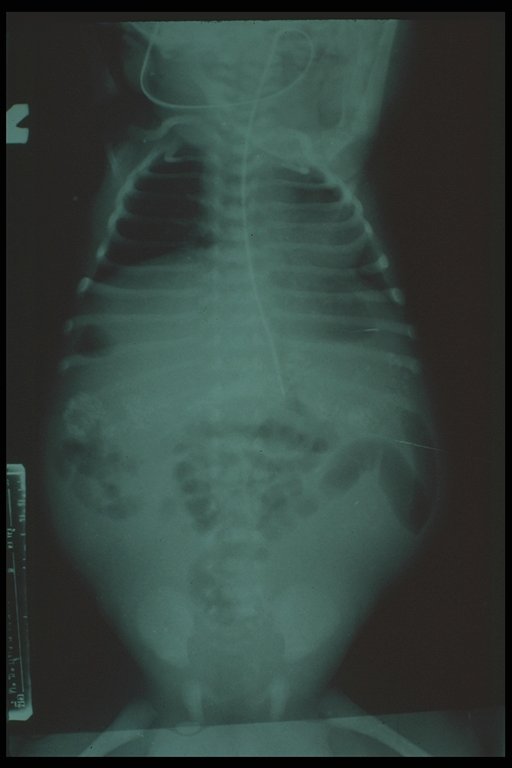

Meconium peritonitis. A classical plain abdominal X-ray demonstrates calcified extravasated meconium in the peritoneal cavity since fetal growth. Free air in the abdomen (football sign) is also noted